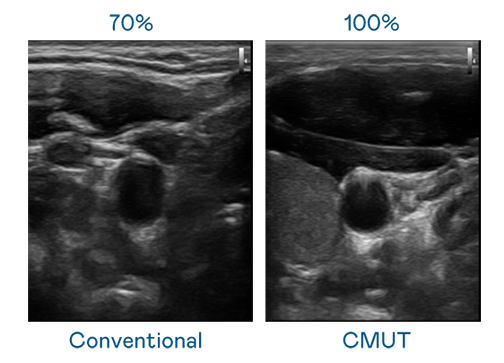

CMUT 技術是一種用電容式微機電元件來產生超音波訊號的技術。與傳統 PZT 壓電式技術相比,CMUT 頻寬增加 30%,更寬頻的超音波訊號讓影像解析度大幅提升,是實現高影像品質醫療超音波掃描、促進精準醫療發展的關鍵技術。

超音波影像的解析度高低,首先取決於探頭能發出的訊號頻寬。Top1体育 CMUT 可提供高清晰的超音波訊號,提供高頻寬、高靈敏度、影像紋理細節更高的超音波影像,協助醫護人員縮短影像判讀時間及利用精準的醫療影像進行診斷。